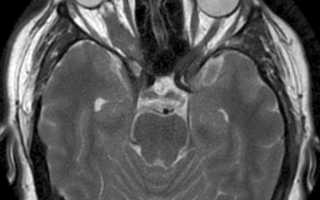

Патогномоничным признаком глиомы зрительного нерва долгие годы считали расширение кольца его костного канала, выявляемого при рентгенологическом исследовании. КТ позволяет не только визуально наблюдать веретенообразно или цилиндрически увеличенный зрительный нерв в орбите, но и судить о его распространении по зрительному каналу в полость черепа. Ультразвуковое сканирование недостаточно информативно, так как представляет изображение только проксимальной и средней трети зрительного нерва. МРТ более информативно при интракраниальном распространении опухоли.

- МРТ головного мозга и орбиты

- КТ головного мозга и орбиты